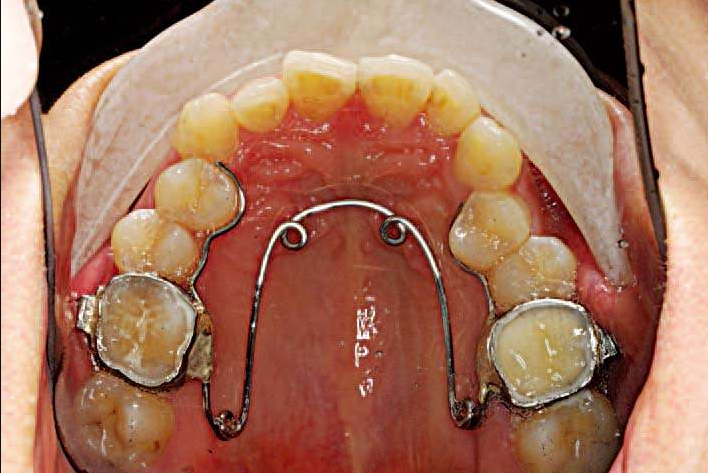

(2)上颌Nance托,下颌舌弓

除了对恒牙萌出有影响之外,当乳牙Ⅳ、Ⅴ早失时恒牙6很容易近中前移,造成牙弓内间隙丢失,临床上很多的牙齿拥挤都是这个原因。

这时候,上颌Nance托,下颌舌弓是比较好的牙弓间隙保持的方法。